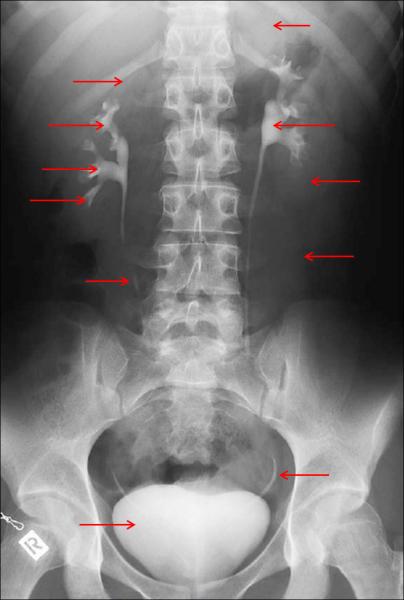

Anatomía radiológica en una urografía excretora normal.

por Silvana Ciardullo

1 Riñón izquierdo, polo superior 2 Riñón derecho, polo superior 3 Grupo calicial superior 4 Grupo calicial medio 5 Grupo calicial inferior 6 Pelvis renal 7 Riñón izquierdo, polo inferior 8 Margen del psoas 9 Uréter 10 Uréter distal 11 Vejiga urinaria